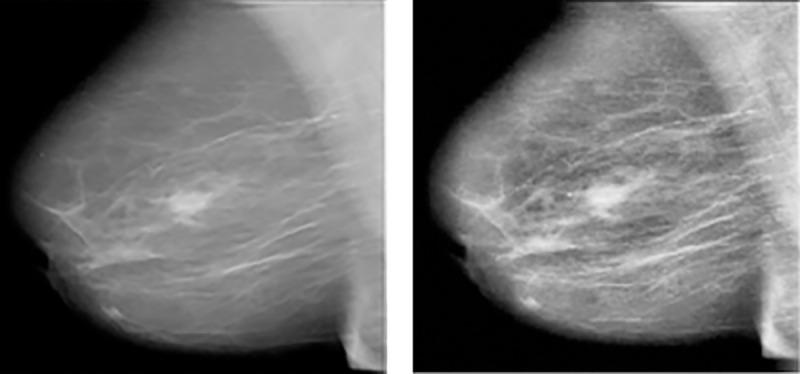

The real cause of breast cancer is very challenging to determine and therefore early detection of the disease is necessary for reducing the death rate due to risks of breast cancer. Early detection of cancer boosts increasing the survival chance up to 8%. Primarily, breast images emanating from mammograms, X-Rays or MRI are analyzed by radiologists to detect abnormalities. However, even experienced radiologists face problems in identifying features like micro-calcifications, lumps and masses, leading to high false positive and high false negative. Recent advancement in image processing and deep learning create some hopes in devising more enhanced applications that can be used for the early detection of breast cancer. In this work, we have developed a Deep Convolutional Neural Network (CNN) to segment and classify the various types of breast abnormalities, such as calcifications, masses, asymmetry and carcinomas, unlike existing research work, which mainly classified the cancer into benign and malignant, leading to improved disease management. Firstly, a transfer learning was carried out on our dataset using the pre-trained model ResNet50. Along similar lines, we have developed an enhanced deep learning model, in which learning rate is considered as one of the most important attributes while training the neural network. The learning rate is set adaptively in our proposed model based on changes in error curves during the learning process involved. The proposed deep learning model has achieved a performance of 88% in the classification of these four types of breast cancer abnormalities such as, masses, calcifications, carcinomas and asymmetry mammograms.

乳腺癌的确切病因很难确定,因此早期发现疾病对于降低乳腺癌死亡率至关重要。癌症的早期发现可以提高 8%的生存率。放射科医生主要通过分析乳房 X 光片、X 光或 MRI 产生的乳房图像来检测异常。然而,即使是经验丰富的放射科医生在识别微钙化、肿块和肿块等特征时也会遇到问题,导致高假阳性和高假阴性。图像处理和深度学习的最新进展为设计更多增强型应用程序带来了一些希望,这些应用程序可用于早期发现乳腺癌。在这项工作中,我们开发了一种深度卷积神经网络(CNN),用于分割和分类各种类型的乳房异常,如钙化、肿块、不对称和癌,与现有的主要将癌症分为良性和恶性的研究工作不同,这可以改善疾病管理。首先,我们在自己的数据集上使用预训练模型 ResNet50 进行了迁移学习。类似地,我们开发了一种增强型深度学习模型,其中学习率被认为是训练神经网络时最重要的属性之一。在我们提出的模型中,根据学习过程中误差曲线的变化自适应地设置学习率。所提出的深度学习模型在对肿块、钙化、癌和不对称乳房 X 光等四种乳腺癌异常类型的分类中取得了 88%的性能。